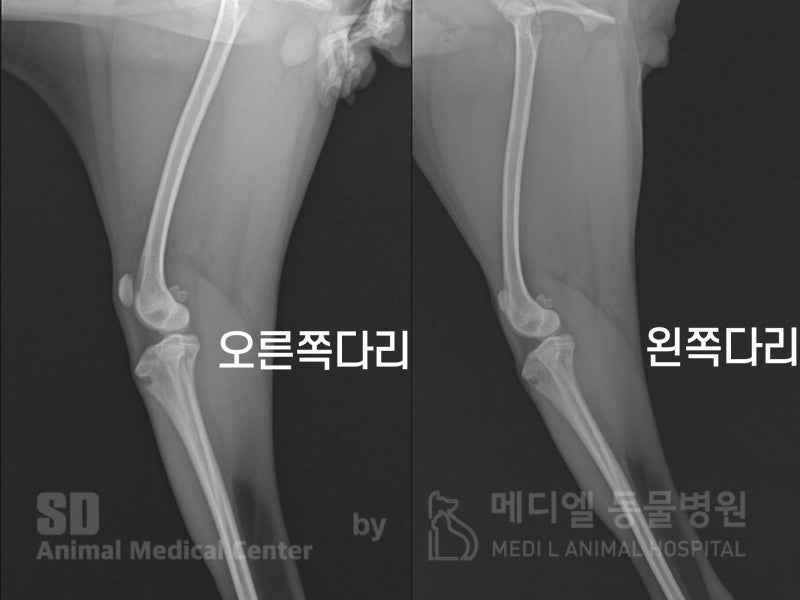

병원에서 촬영 방사선 사진입니다. 정상위치(무릎의 중간)에 있어야 할 슬개골이 안쪽으로 빠져있는게 확인됩니다.

이럴 경우 내측성 슬개골 탈구로 진단되며, 방치하게 될 경우 관절염이나, 전십자인대단열까지도 진행될 수 있습니다.